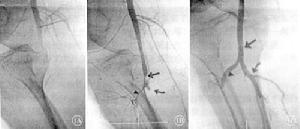

3.動脈造影檢查造影是栓塞定位最正確方法,大多數病人根據臨床症狀和體徵以及都卜勒超聲就能做出診斷。僅在診斷上有疑問,或在取栓術後必須了解動脈是否通暢才進行動脈造影。